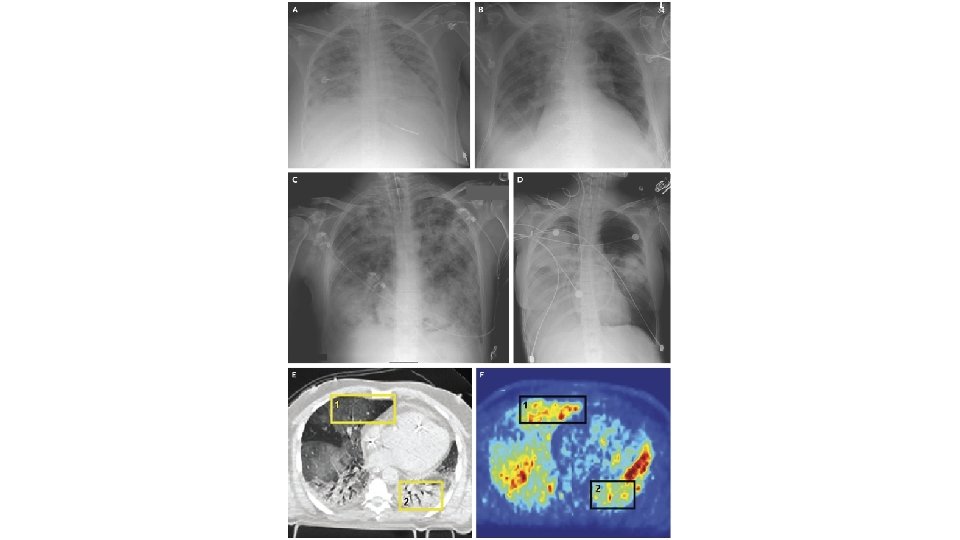

Acute Respiratory Distress Syndrome • Bernard GR, Artigas A, Brigham KL, et al. The American-European Consensus Conference of ARDS: definitions, mechanisms, relevant outcomes, and clinical trial coordination. American Journal of Respiratory and Critical Care Medicine. 1994; 149: 818 -824. • • • Acute Onset Bilateral Infiltrates on Chest x-ray Hypoxaemia Pulmonary Artery Occlusion Pressure <18 mm. Hg No validated diagnostic biomarkers are available

Acute Lung Injury <300 mm. Hg Pa. O 2/Fi. O 2 ratio Acute Respiratory Distress Syndrome <200 mm. Hg